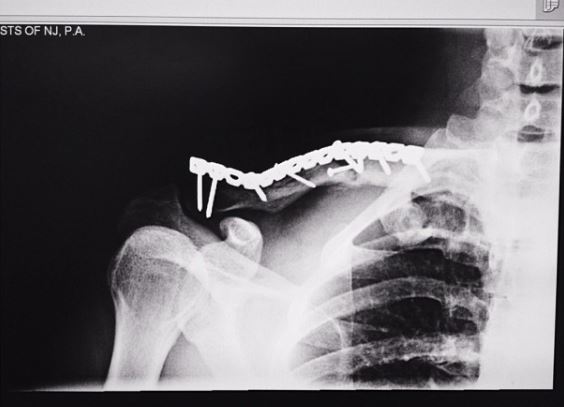

It happened while on the road bike. I went out for a lunch ride and woke up at Hackensack Medical a few hours later. I was knocked out for while. Lost memory or any recollection of the day. So I don't know what really happened. When I regained consciousness, I was staring at a white ceiling with doctors/nurses looking over me. I thought I was abducting by aliens.Oof... we want details!

yikes - thats scary hope it heals fast.It happened while on the road bike. I went out for a lunch ride and woke up at Hackensack Medical a few hours later. I was knocked out for while. Lost memory or any recollection of the day. So I don't know what really happened. When I regained consciousness, I was staring at a white ceiling with doctors/nurses looking over me. I thought I was abducting by aliens.